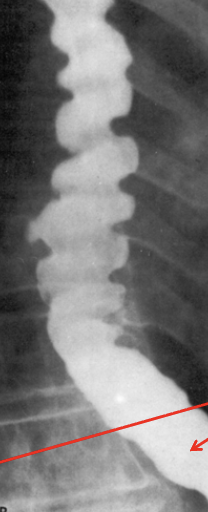

<p>What&nbsp;esophageal disorder is this?</p>

What esophageal disorder is this?

Diffuse esophageal spasm